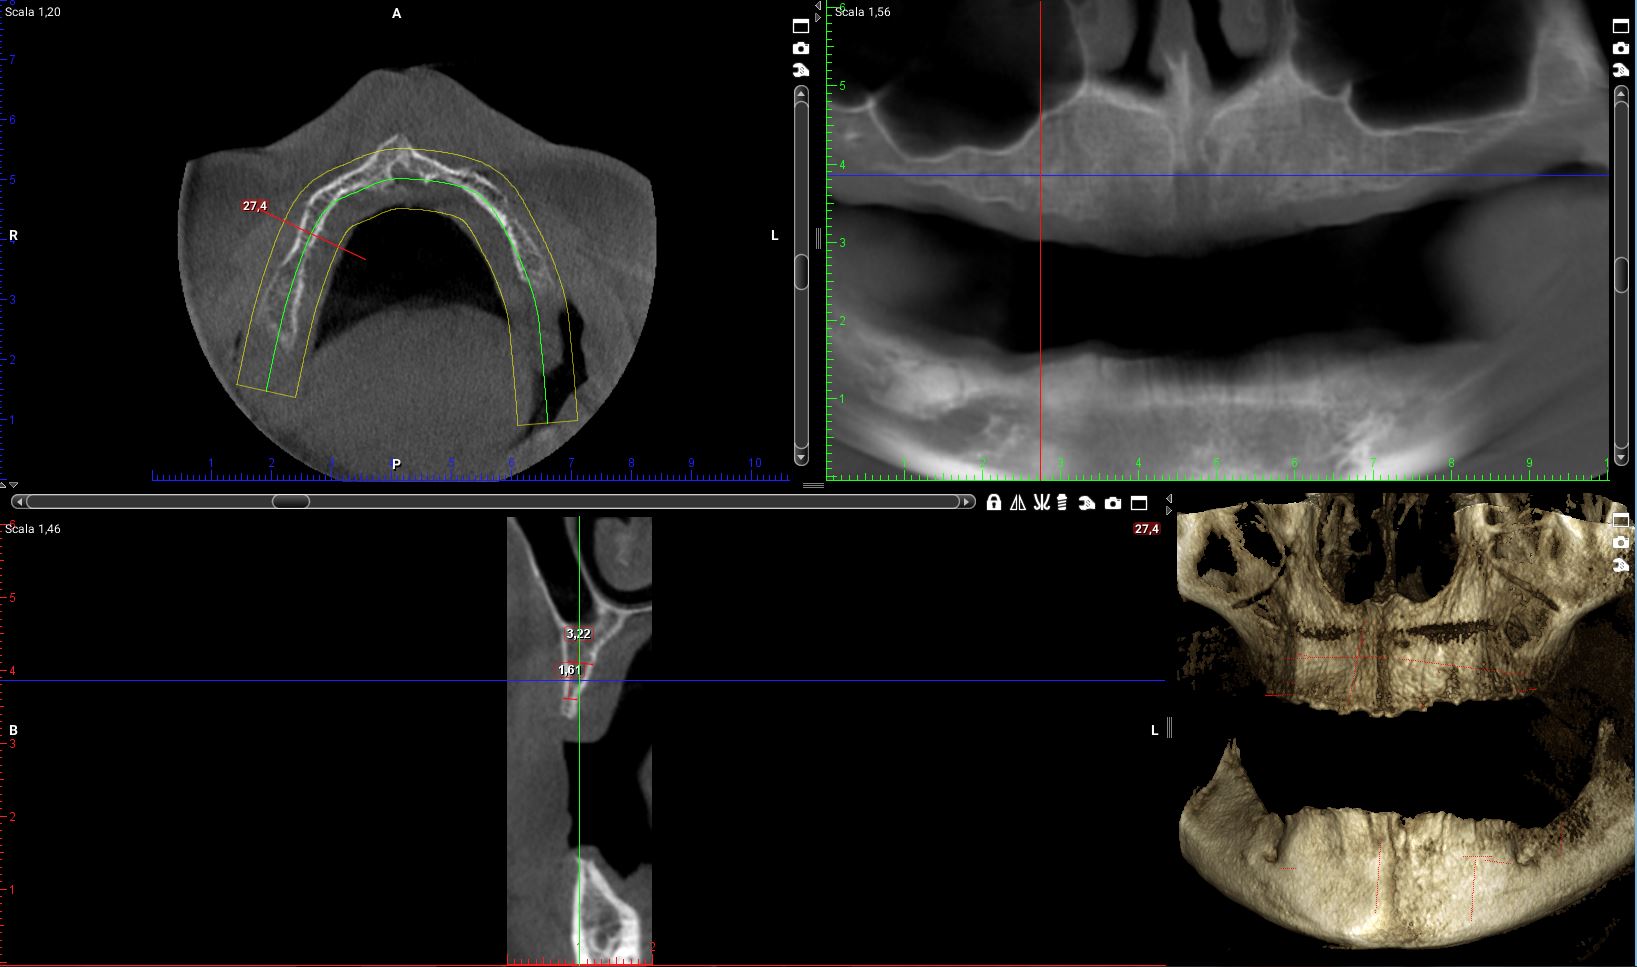

Ora riprendiamo i tagli della cone-beam della mia paziente in corrispondenza delle zone dove dovrò posizionare i quattro impianti.

Impianto distale di destra:la cresta è larga molto meno di 4mm per tutta la sua estensione in altezza. E di lì l’impianto ci deve passare!

se vogliamo ricercare uno spessore di cresta che superi i 4 mm dobbiamo andare a 5mm dal pavimento del naso. Io non farei un carico immediato full-arch su un impianto da 5mm!

Sulla sinistra e pure peggio!

Cosa ho fatto io, invece con la mia paziente!?

Ti faccio vedere.

Eppure l’osso non c’era!!!! O almeno così aveva detto l’interpretazione rigida della simulazione al computer.